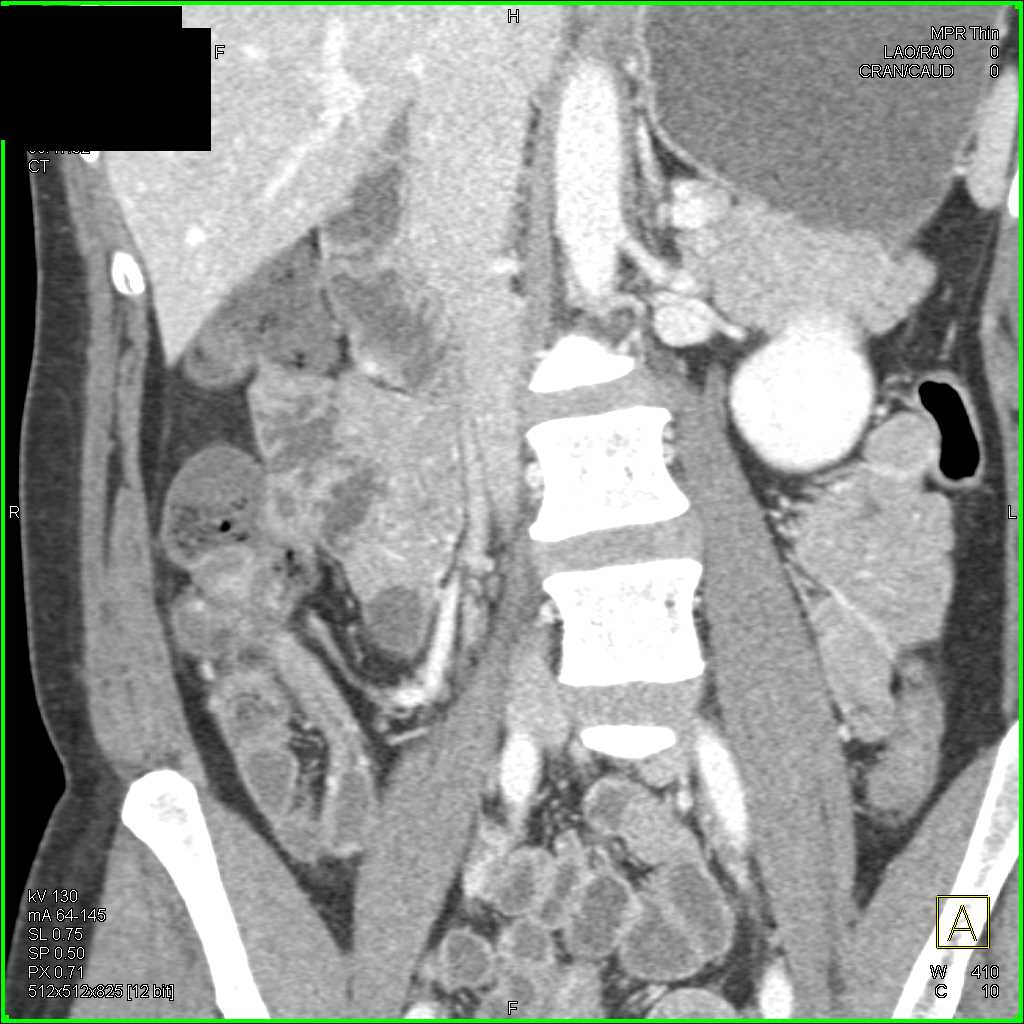

Crohns Disease Terminal Ileum